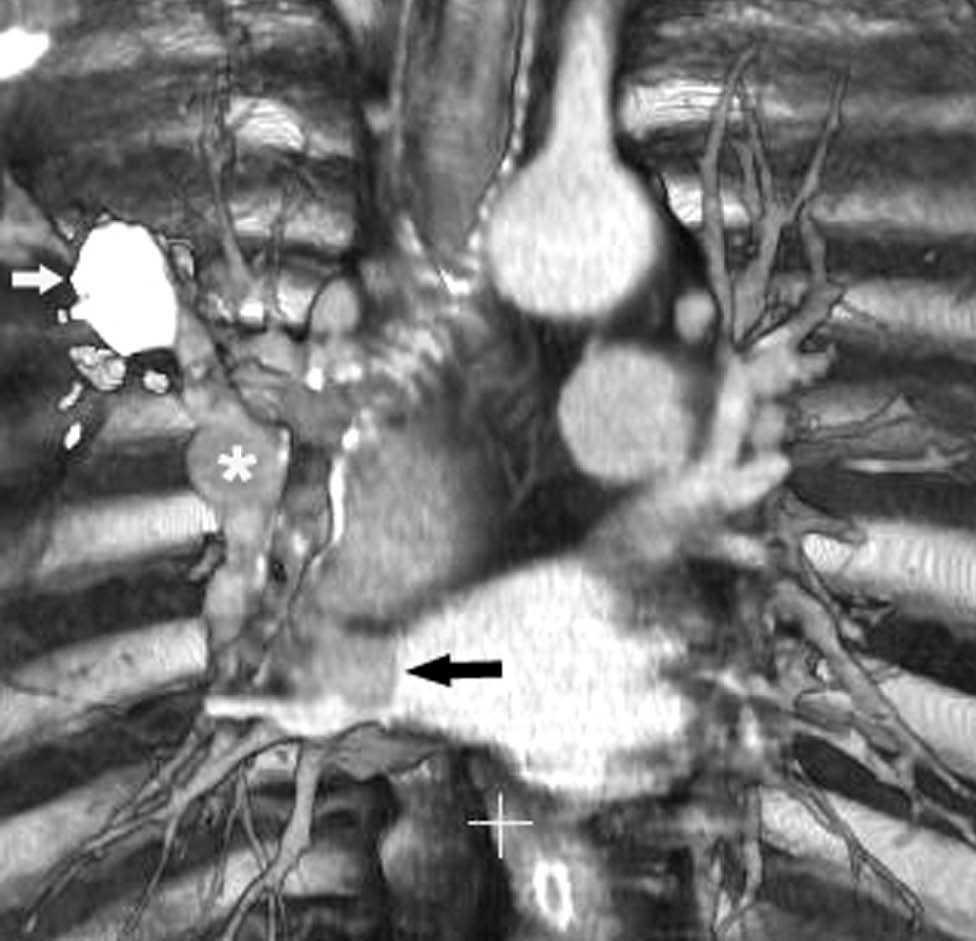

Fig. 11.--N2. (A) Corte axial de tomografía computarizada (TC) con contraste. Nódulo heterogéneo en el segmento 6 del lóbulo inferior derecho con infiltración de la vena pulmonar inferior (flecha). (B) En la reconstrucción de volumen se ponen de manifiesto la infiltración tumoral de la vena pulmonar (flecha negra), la adenopatía hiliar (asterisco) y una adenopatía calcificada lobar superior derecha (flecha blanca).

Fig. 12.--Estaciones ganglionares para la estadificación del cáncer de pulmón. Las reconstrucciones multiplanares (MPR) son de gran ayuda para precisar los territorios ganglionares afectos. Correlación de los territorios ganglionares entre el mapa ganglionar de Mountain y Dressler y una reconstrucción coronal de un paciente con afectación adenopática mediastínica e hiliar bilateral. (A y B) Ganglios mediastínicos superiores e inferiores e hiliares. (C y D) Ganglios aórticos. AP: arteria pulmonar. Ao: aorta.

La precisión de la TC para predecir la afectación ganglionar mediastínica, pese a la ayuda que suponen las reconstrucciones MPR y 3D en la valoración de determinados territorios ganglionares (espacio subcarinal, hilio o ventana aortopulmonar) (fig. 11), sigue teniendo muchas limitaciones. El único criterio que se emplea para considerar que un ganglio es patológico es el tamaño (cuando el eje corto es mayor de 10 mm, salvo en el espacio subcarinal que se acepta hasta 12 mm). El empleo únicamente de criterios de tamaño hace que la TC sea una técnica poco precisa en la valoración de la afectación ganglionar. En un metaanálisis reciente13 la sensibilidad global de la TC para estadificar el mediastino fue de un 57%, con una especificidad del 82%, un valor predictivo positivo (VPP) del 56% y un valor predictivo negativo (VPN) del 83%. Lo que es innegable es la capacidad de la TC para mostrar un mapa de los ganglios tanto hiliares como mediastínicos (fig. 12), lo cual es de gran utilidad en la determinación del factor N. La valoración del territorio hiliar puede ser compleja por la agrupación de estructuras vasculares, por lo que además de la opacificación adecuada de éstas, es de utilidad la identificación de la pérdida del ángulo de la bifurcación (carina secundaria), ya que el eje corto significativo en este territorio es de 3 mm. Como ya hemos comentado, también es de gran ayuda en esta localización el empleo de reconstrucciones (fig. 11)5.